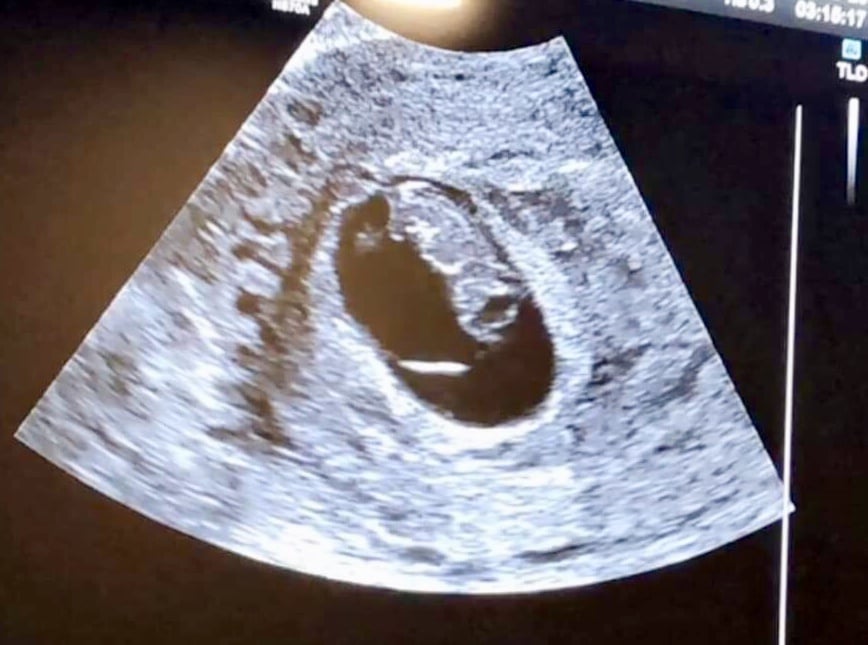

Hi everyone! My EDD is 7/1/2019, so I’m not sure if I’ll be here or in June. Here is our ultrasound photo from 8 weeks (transvaginal) a couple weeks ago. Heartbeat was 172bpm. Baby is the blob on the upper right, facing away.

Here is our ultrasound photo from 8 weeks (transvaginal) a couple weeks ago. Heartbeat was 172bpm. Baby is the blob on the upper right, facing away.